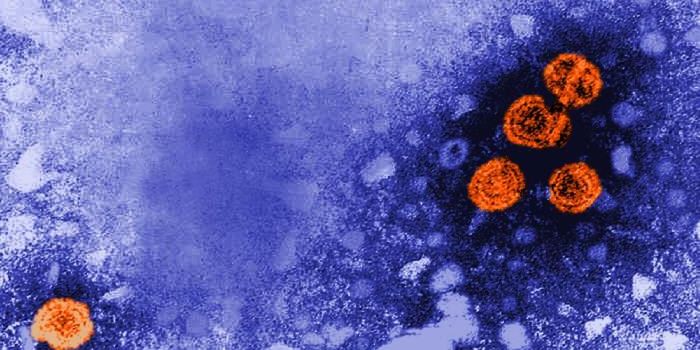

NOV 29, 2021MicrobiologyIt's estimated that about 240 million people worldwide have an HBV infection. Hepatitis B infections are linked to t ...

SEP 28, 2021ImmunologyHepatitis B infections have created a ‘silent epidemic’—infected people don’t display any sympto ...

JUL 26, 2021MicrobiologyThe hepatitis B virus was discovered by Dr. Baruch Blumberg in 1967. World hepatitis day is commemorated on his birthday ...